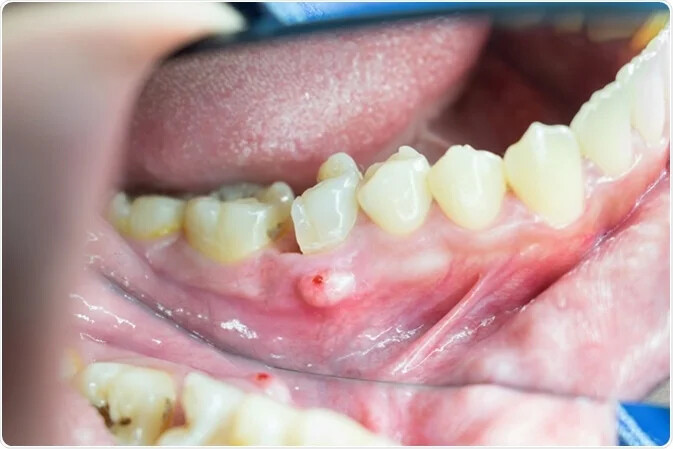

Apical periodontitis refers to the inflammation of the periodontium — the tissue that surrounds your teeth. Apical means "relating to the apex," so inflammation usually occurs around the tip — or apex — of the tooth's root. Two types of apical periodontitis exist:

Typically, apical periodontitis occurs when there's another problem with the tooth. For example, inflammation can develop if a person has an untreated cavity. In some cases, apical periodontitis can develop if the pulp of the tooth becomes infected or dies. Injury or trauma to the tooth can also lead to apical periodontitis.

Apicoectomy. If the infection develops or continues after the root canal, you might require an apicoectomy. During this procedure, the endodontist removes the tip of the tooth's root and infected tissue, then seals the end of the root with a filling.